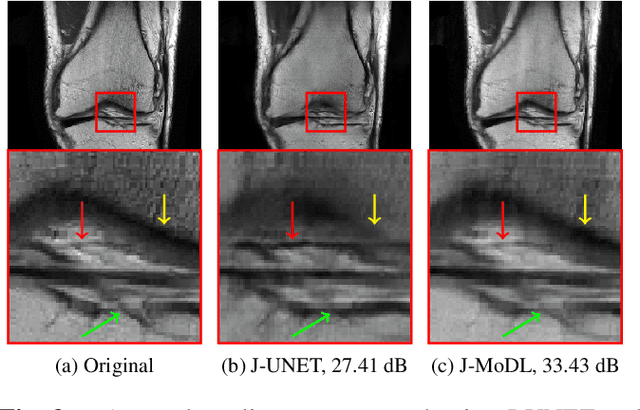

Abstract:Multichannel imaging techniques are widely used in MRI to reduce the scan time. These schemes typically perform undersampled acquisition and utilize compressed-sensing based regularized reconstruction algorithms. Model-based deep learning (MoDL) frameworks are now emerging as powerful alternatives to compressed sensing, with significantly improved image quality. In this work, we investigate the impact of sampling patterns on the quality of the image recovered using the MoDL algorithm. We introduce a scheme to jointly optimize the sampling pattern and the reconstruction network parameters in MoDL for parallel MRI. The improved decoupling of the network parameters from the sampling patterns offered by the MoDL scheme translates to improved optimization and thus improved performance. Preliminary experimental results demonstrate that the proposed joint optimization framework significantly improves the image quality.